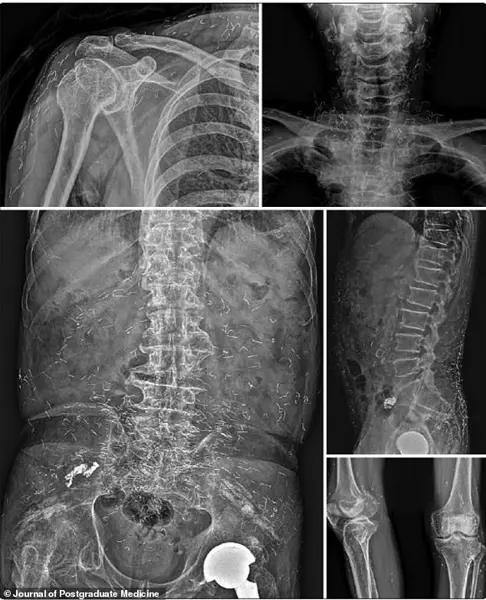

In 2022, a 73-year-old Korean man was hospitalized for a stroke, a condition that, on the surface, seemed unrelated to his decades-long use of gold thread acupuncture.

During his evaluation, he revealed a 30-year history of widespread joint pain, which he had self-treated with the procedure.

X-rays revealed a startling discovery: thousands of tiny gold threads were embedded throughout his body.

His symptoms, including dizziness and pain, had persisted for years, and he had never been diagnosed with rheumatoid arthritis, a condition that was only confirmed after proper medical intervention.

His recovery only began once he received appropriate medication for the newly diagnosed autoimmune disorder.